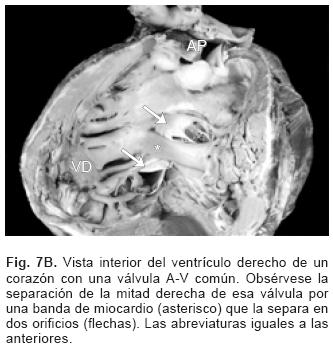

La anatomía básica de los 2 tipos de DSA–V fue la misma. Todos presentaron anillo fibroso A–V común, reducción de la distancia A–V–ápex e incremento de la distancia ápex –válvula aórtica, el tabique ventricular estuvo excavado (Figs. 4 y 6C), el anillo fibroso mostró dilatación anteroposterior, desencuñamiento aórtico, alteración en el esqueleto fibroso del corazón consistente en un anillo fibroso A–V común, ausencia del septum membranoso y persistencia de la continuidad entre la válvula aórtica y la válvula A–V común o válvula A–V izquierda (Fig. 6D), desviación anterior del tracto de salida del ventrículo izquierdo (Figs. 4 y 6C) y en dos especímenes obstrucción de éste por inserción en su interior de la valva anterosuperior izquierda (Fig. 7A). En un espécimen con una válvula A–V común se desarrolló una banda anómala de miocardio entre la pared libre y el tabique ventricular, lo que separó el componente derecho de la válvula A–V común en dos orificios valvulares (Fig. 7B). Las alteraciones asociadas se consignan en la Tabla III.